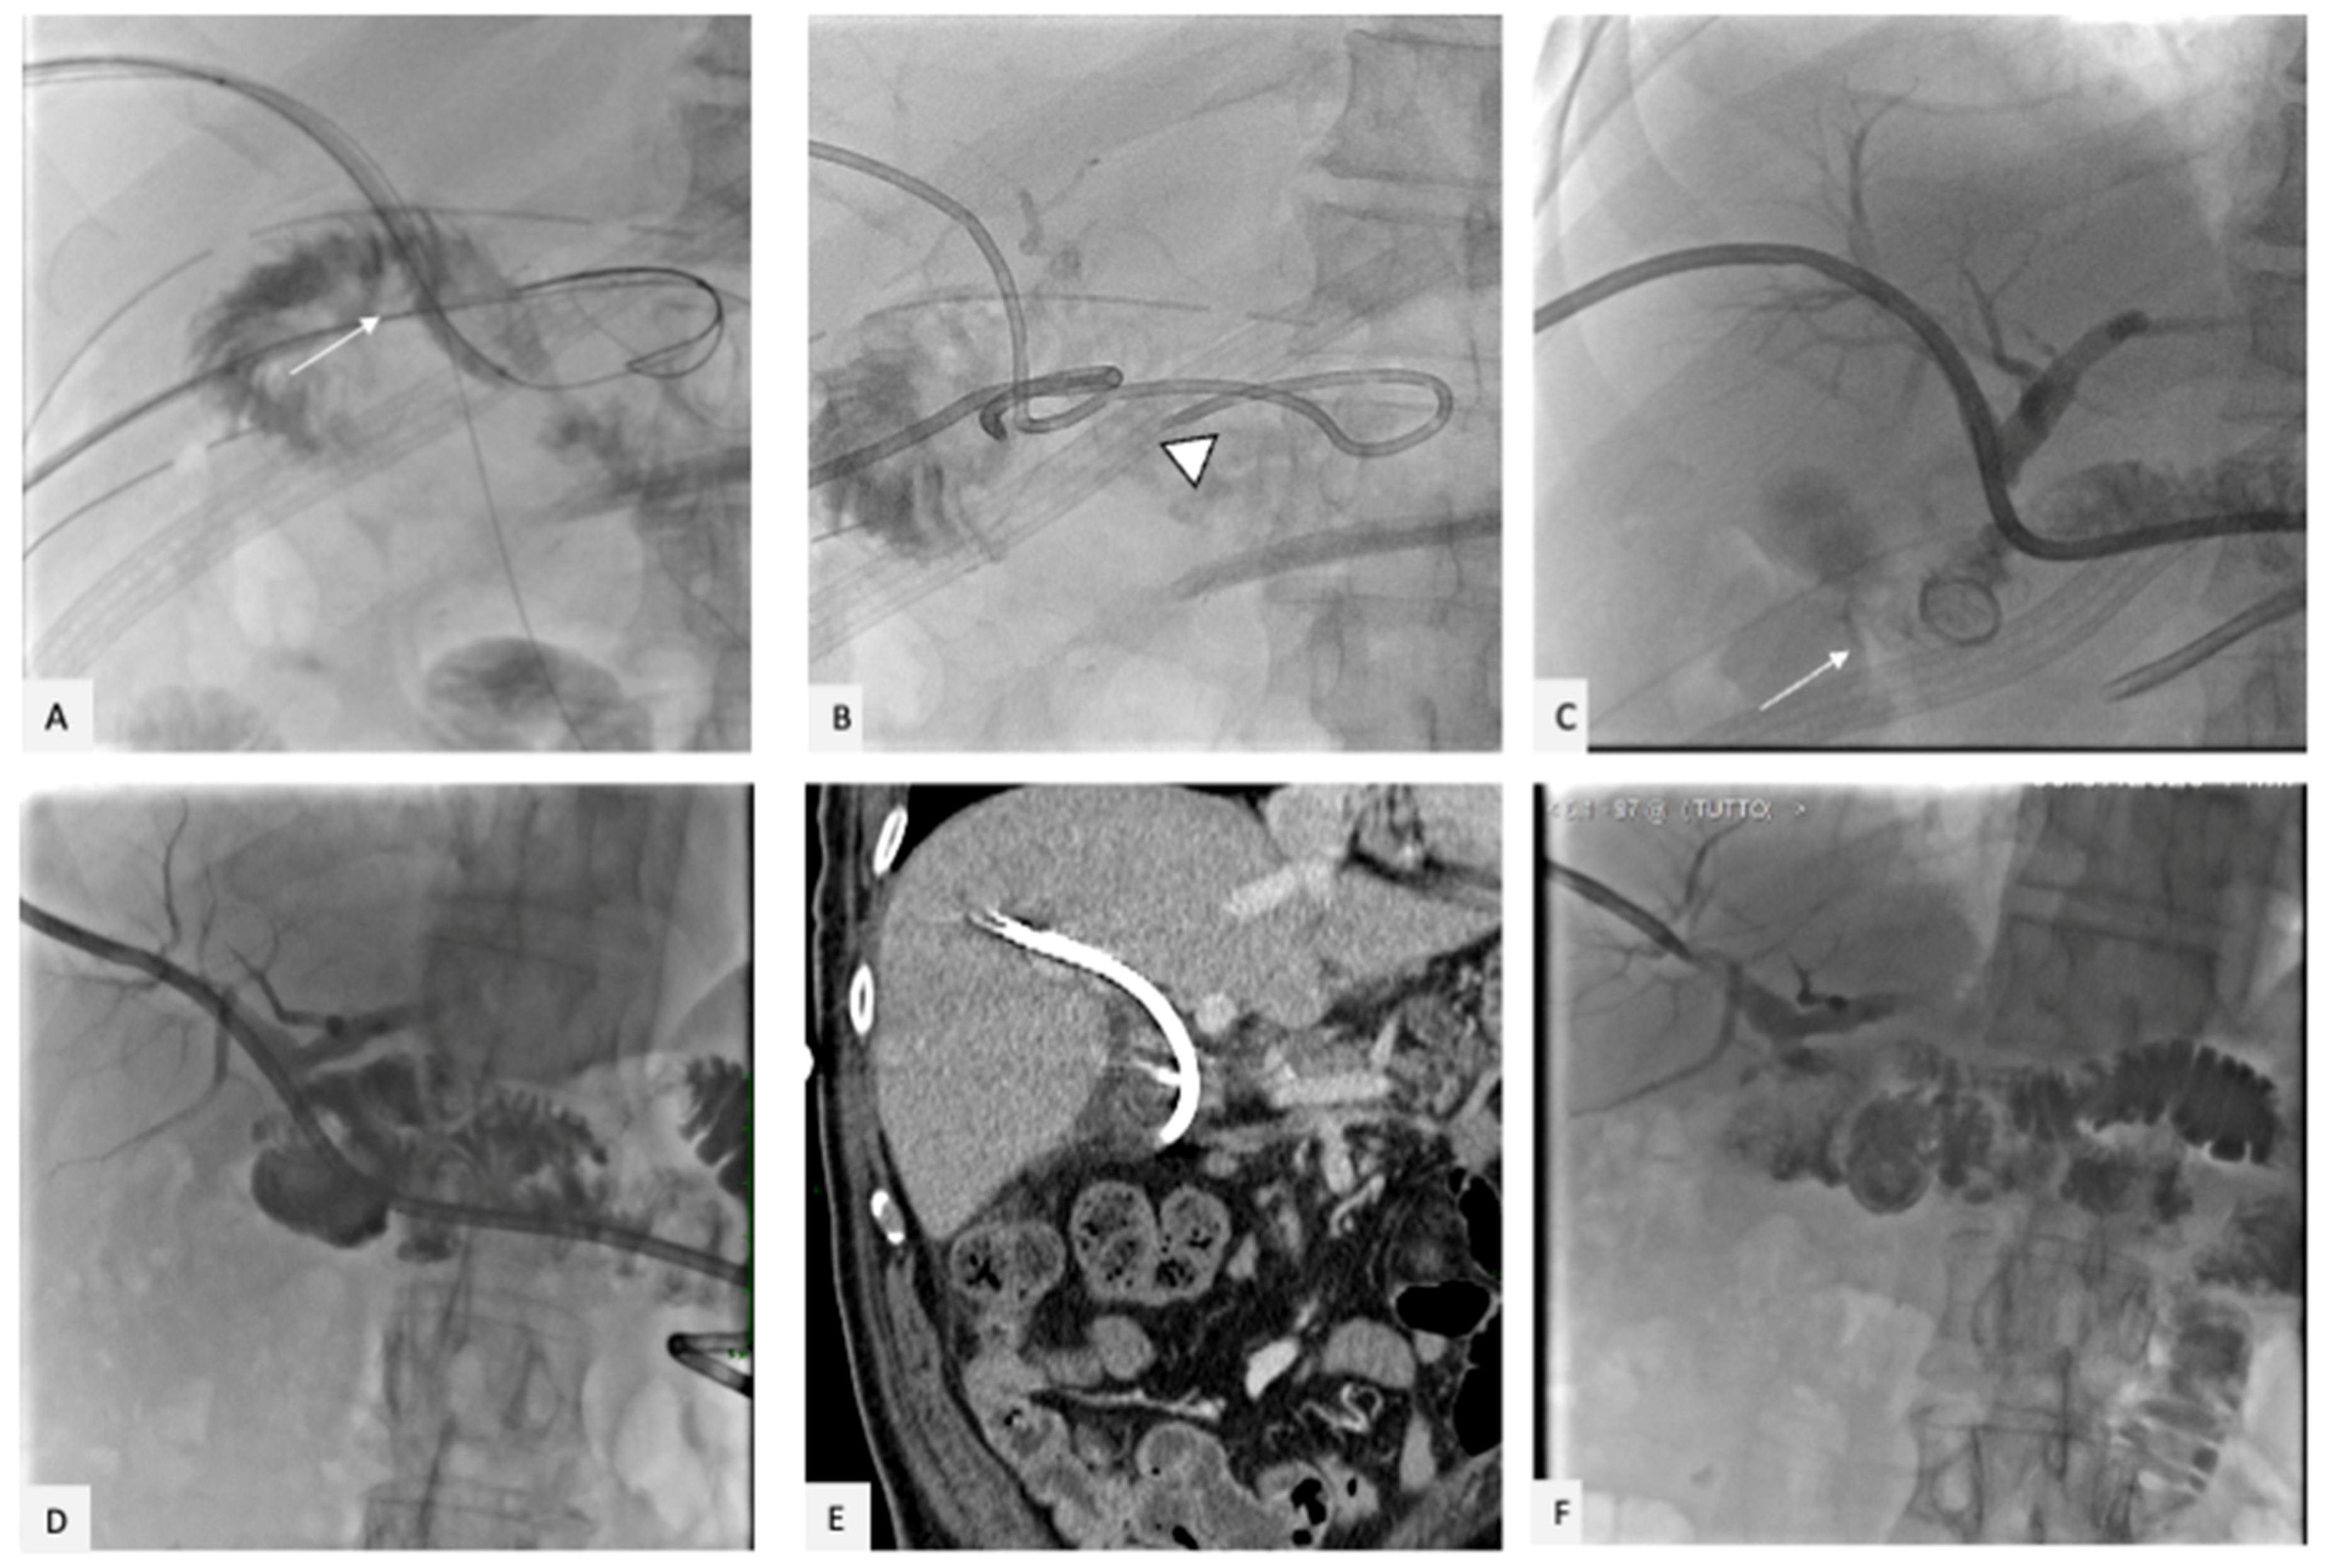

2. Case Presentation